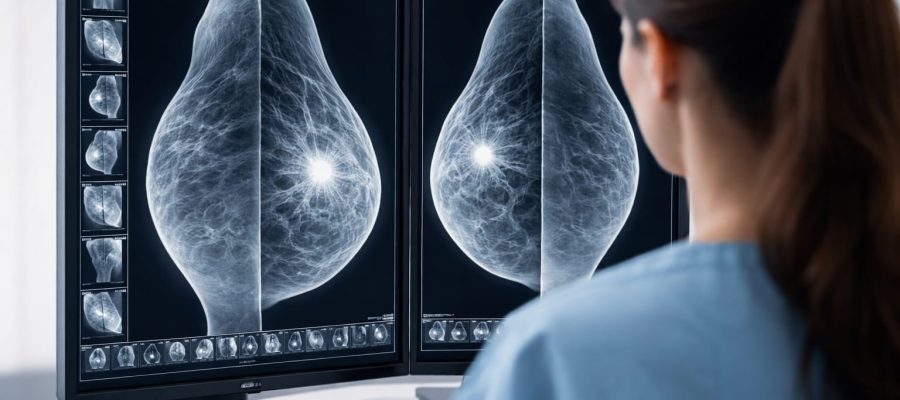

Meme tomosentezinde, X ışını tüpü her bir göğüsten farklı açılardan birçok görüntü yakalayan bir yay içinde hareket eder.

Bu dijital görüntüler daha sonra bir bilgisayar tarafından üç boyutlu görüntüler halinde yeniden “sentezlenir” Bu üç boyutlu görüntü setleri, kanser hücrelerini gizleyebilecek doku örtüşmelerini en aza indirmektedir.

Dijital meme taramasının geldiği nokta olan tomosentezde yapılan meme taraması dijital mamografi için yapılan taramayla aynı süreçlere sahiptir. Bu tarama yönteminde, hastanın memesi iki plastik tabaka arasına yerleştirilir; hastanın ve dolayısıyla memenin hareket etmesini önlemek amacı ile sabitleme yapılır. Işın tüpü meme dokusunun çevresinde hareket eder ve saniyeler içinde çekim işlemi tamamlanır. Çekim bittiği andan itibaren sonuçlar dijital ortama gönderilir. Dijital ortamda memenin üç boyutlu (3D) görüntüleri hazırlanır.

Üç boyutlu görüntüler, uzman doktorun sonuçları değerlendirmesinde etkilidir. Tomosentez cihazının meme kanseri tanısı koymada etkili olduğu görüşü gittikçe yaygınlaşmaktadır. Bu nedenle birçok görüntüleme merkezi ve tıbbi kuruluş tarafından kullanılmaktadır.